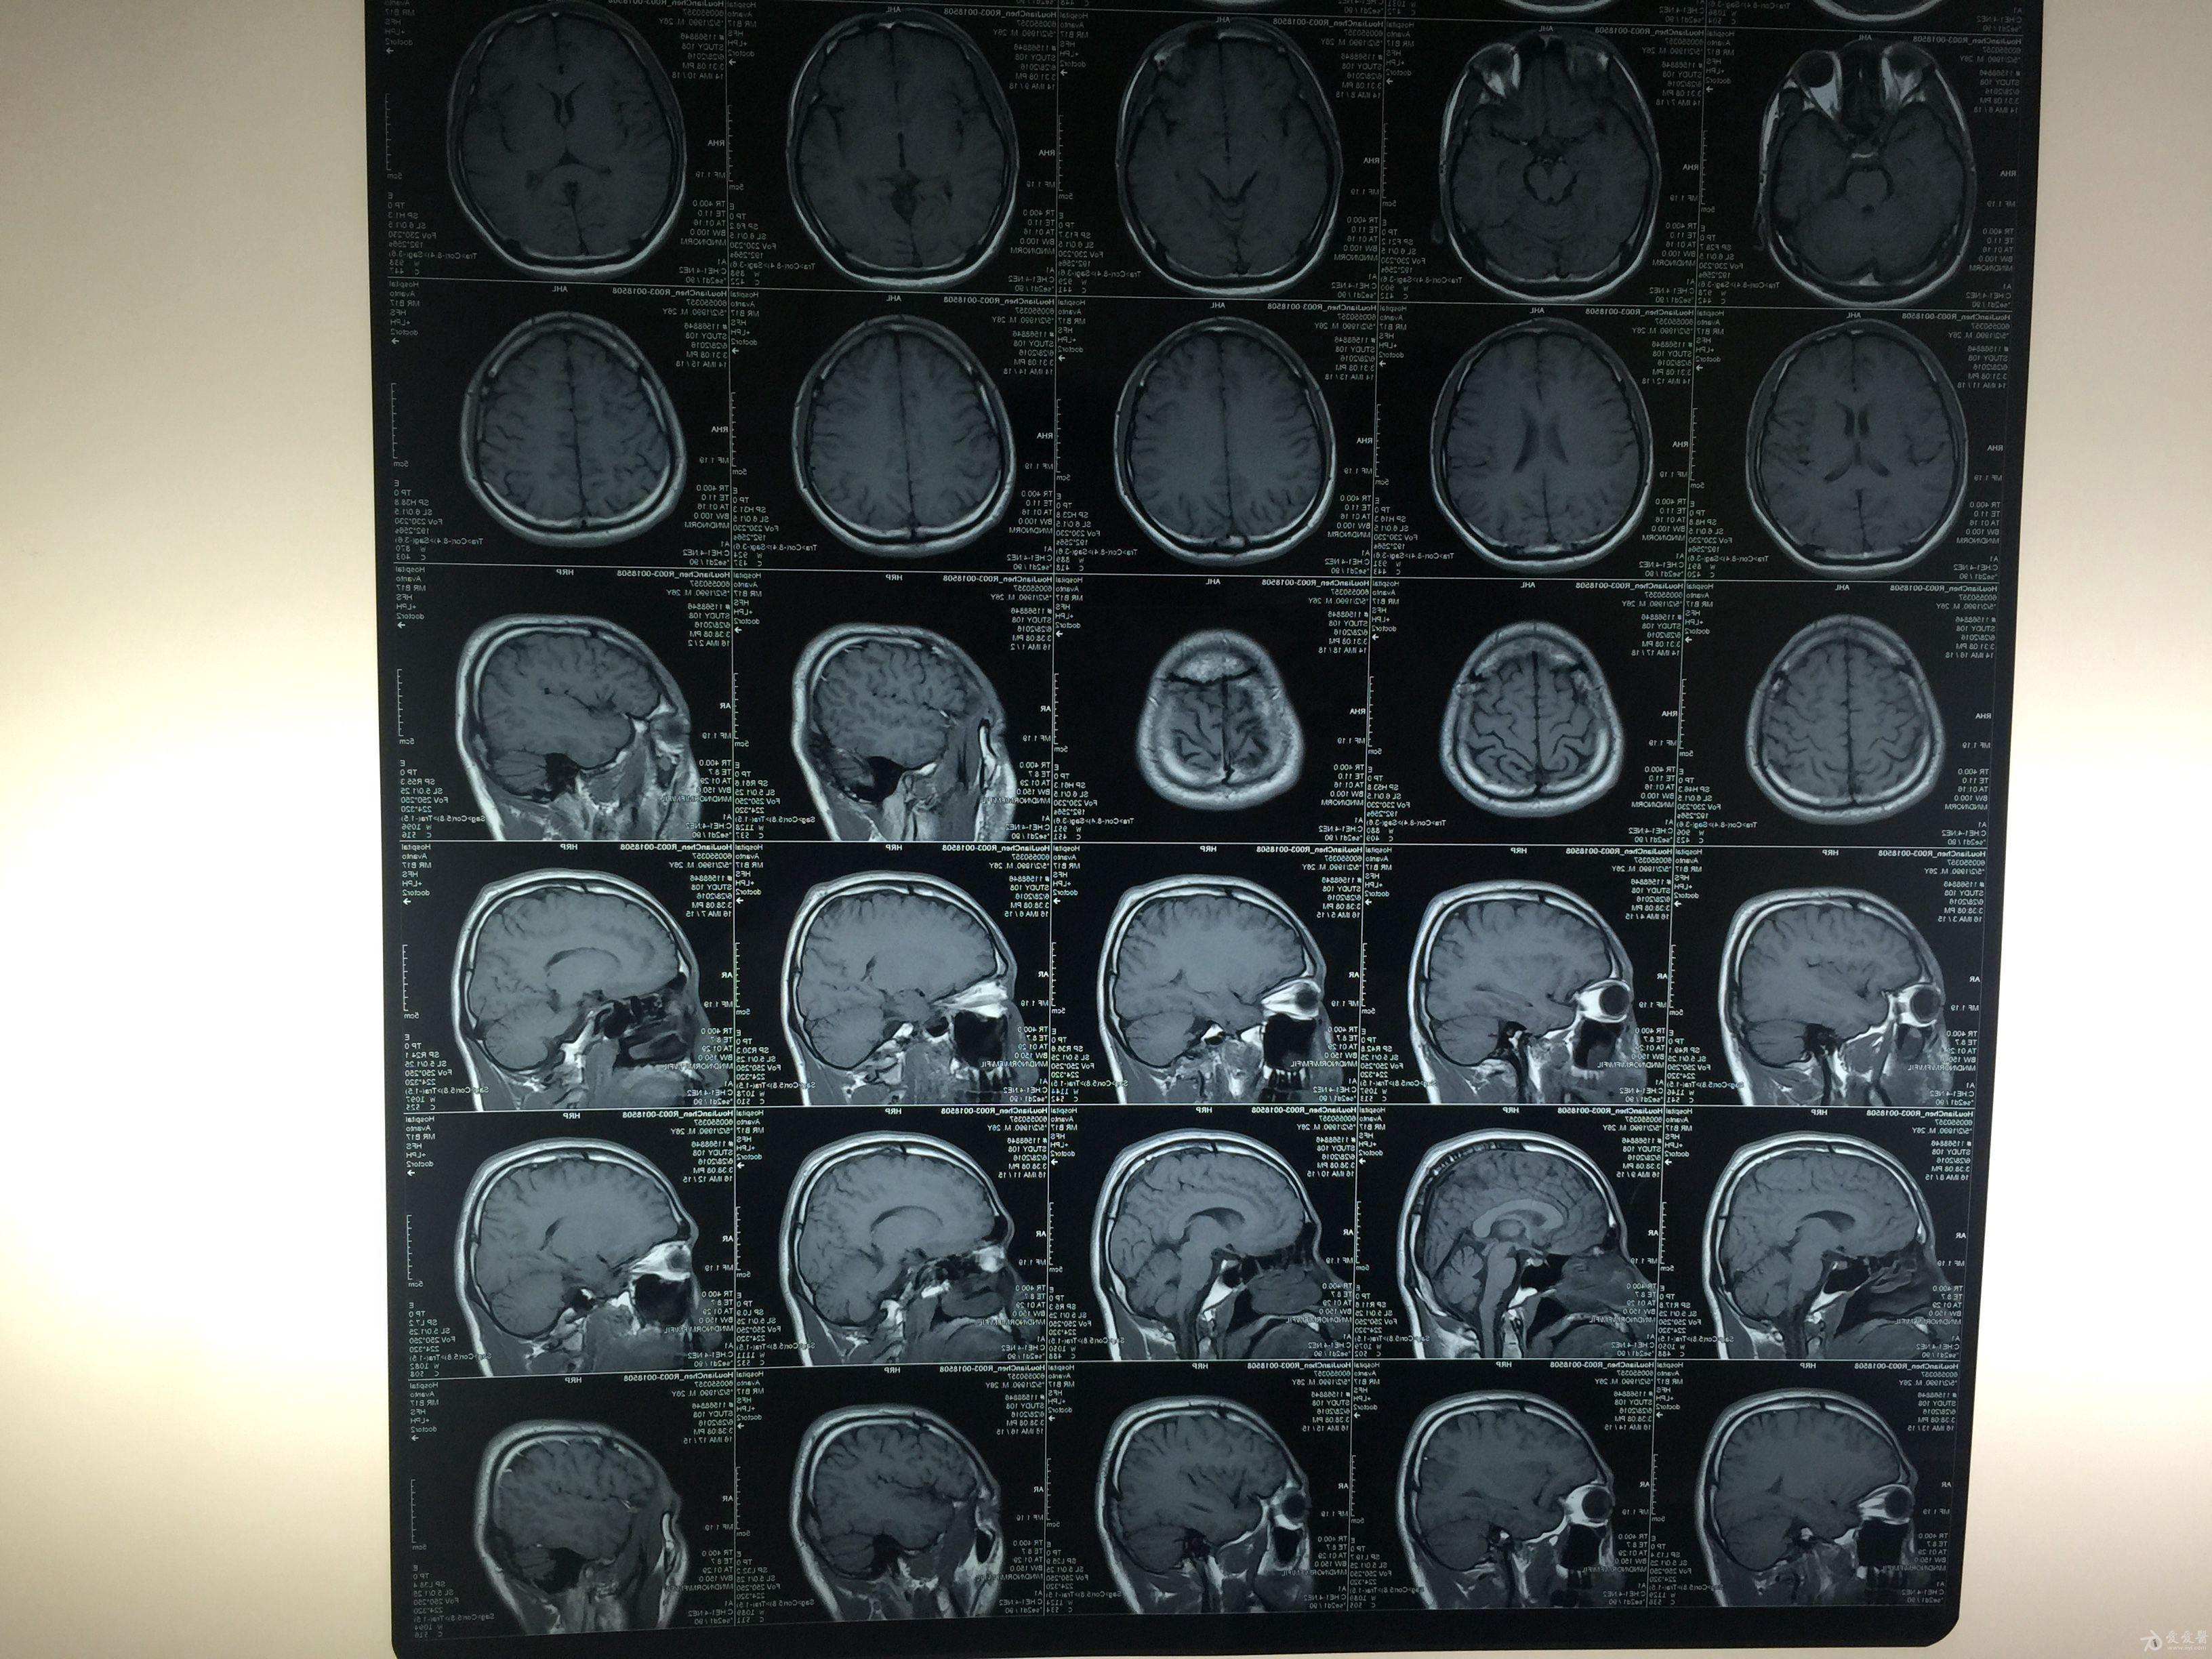

磁共振显示脑组织弥漫性轴索损伤